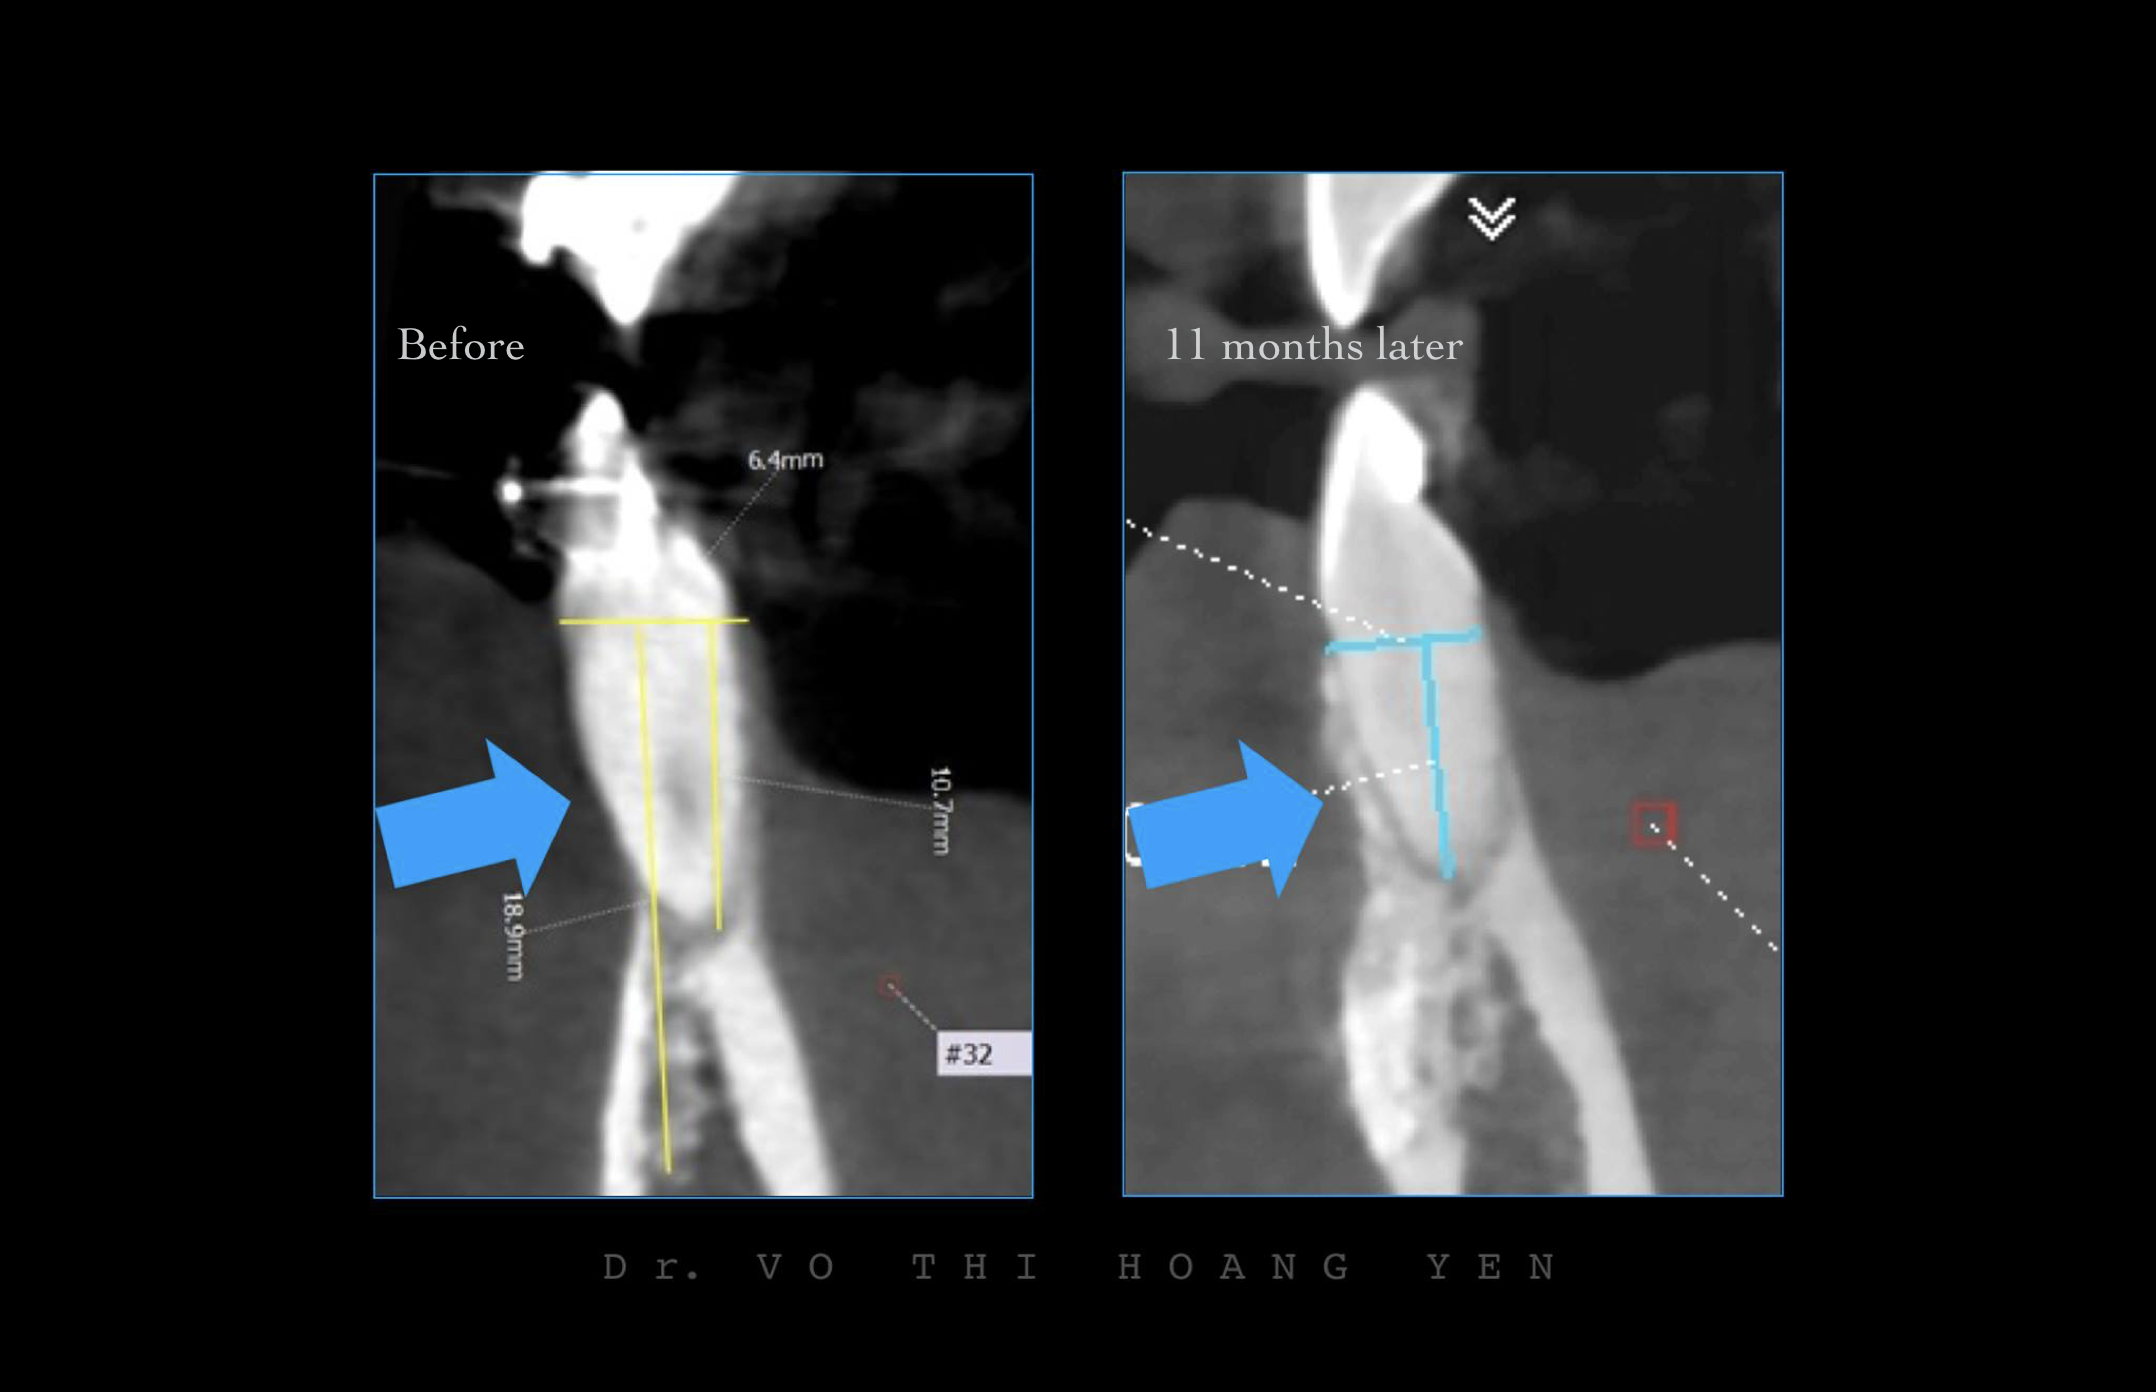

Rất nhiều trường hợp viêm nha chu kết hợp với tình trạng nhiễm trùng tuỷ. Mặc dù sang thương kết hợp có thể có hình ảnh tiêu xương kéo dài, nhưng phần lớn được phát hiện ở giai đoạn sớm, có thể điều trị để giữ răng!